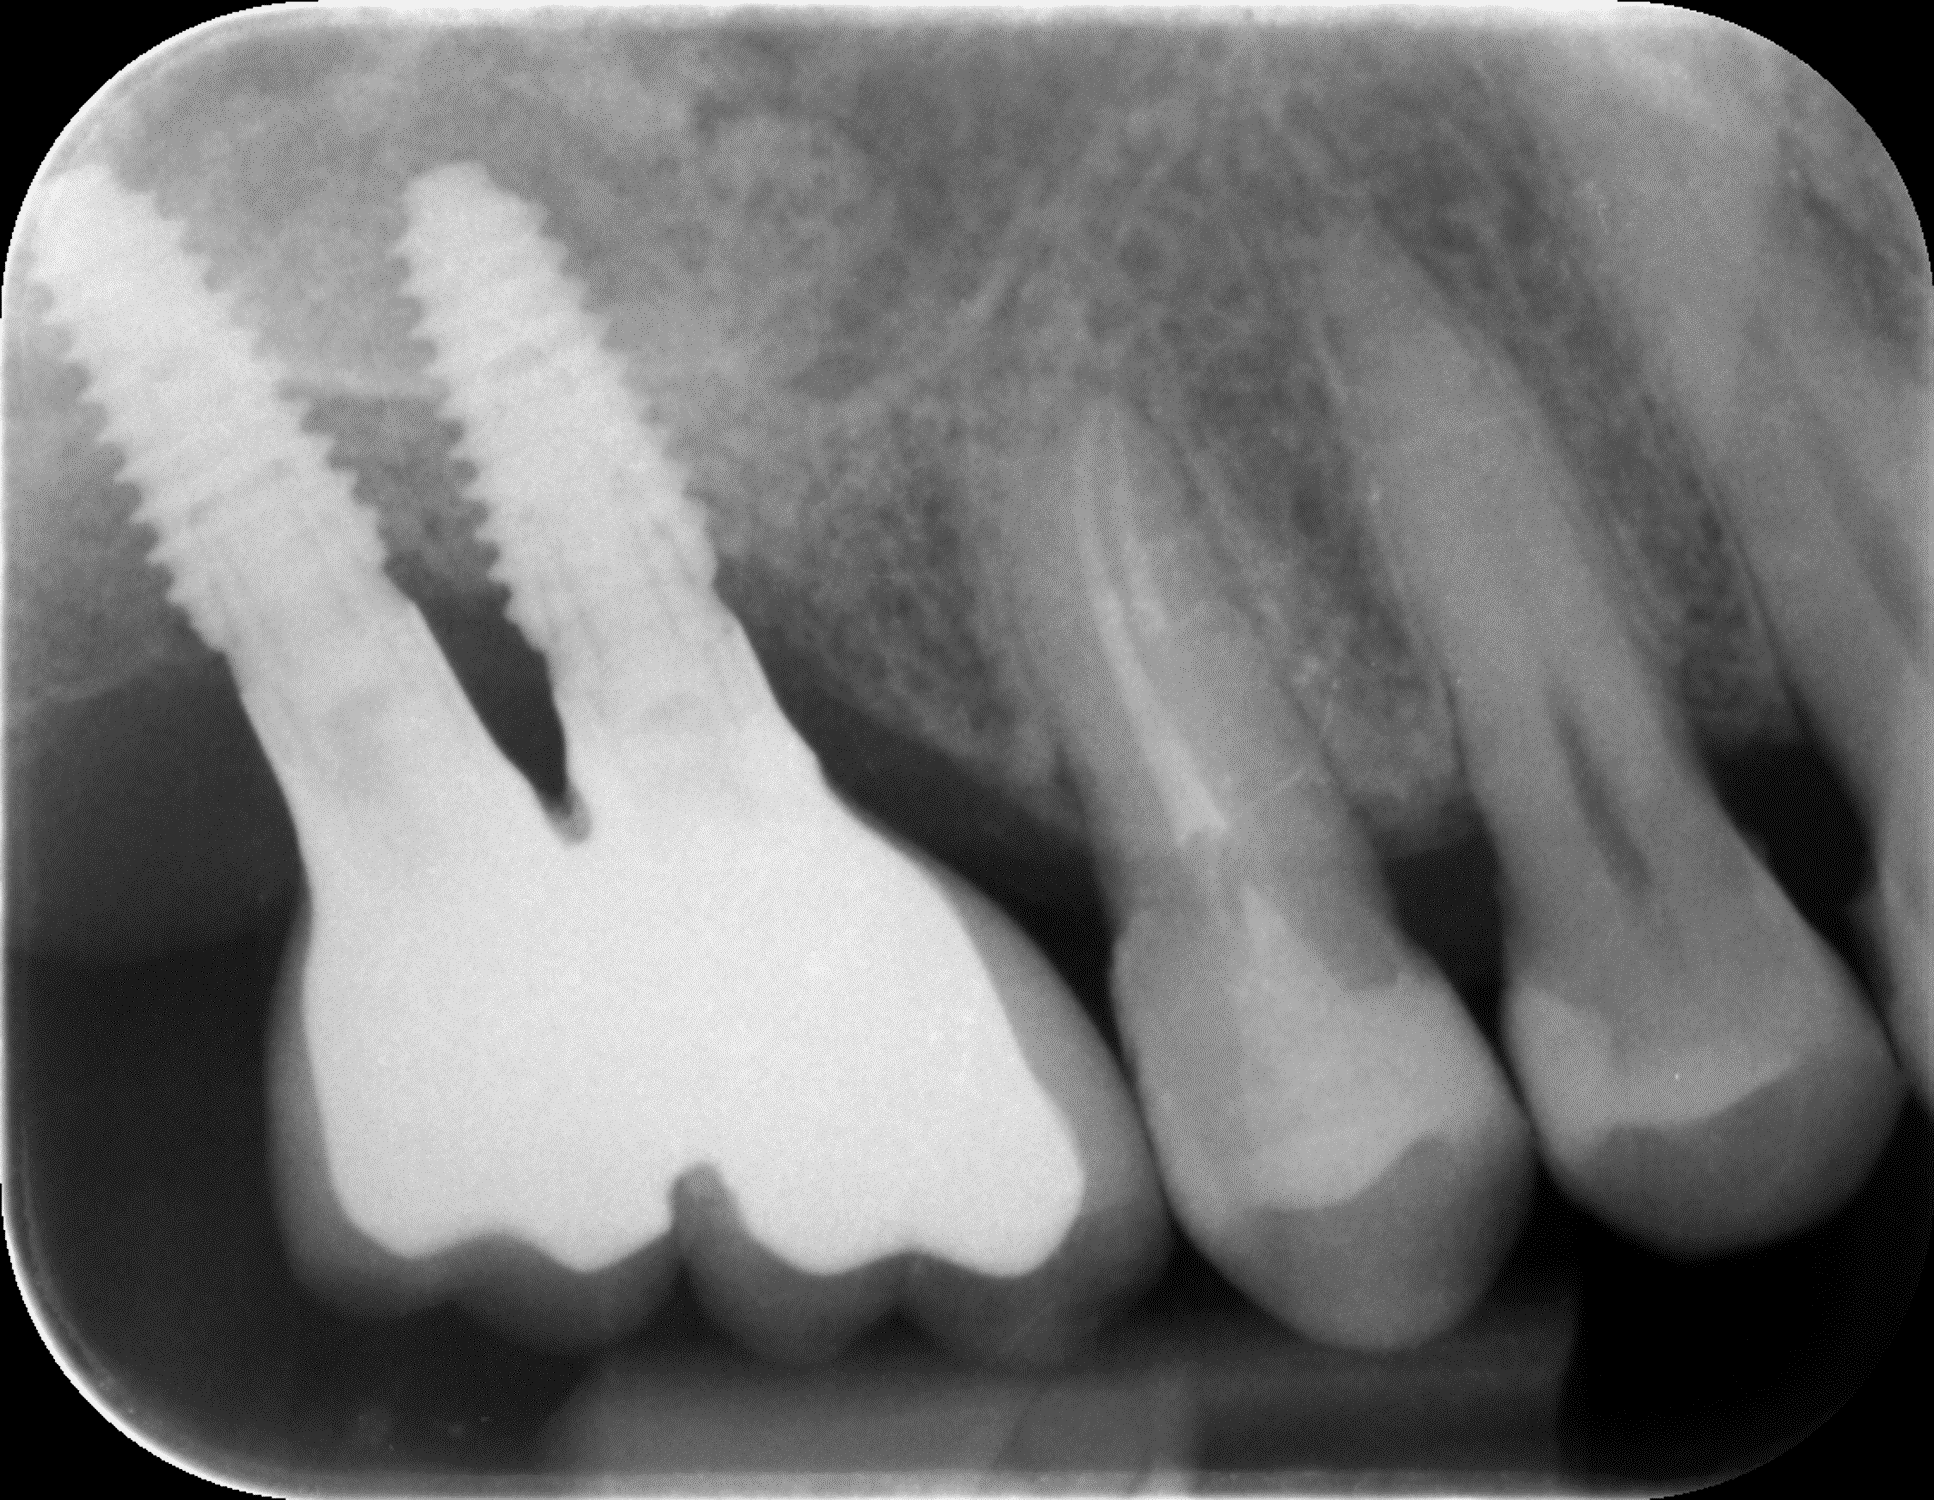

A doua etapă, inserarea implanturilor, a fost realizată după 6 luni.

Împreună cu pacientul, am optat pentru inserarea implantelor cu ajutorul ghidului chirurgical pentru a plasa implantul în poziția protetică ideală și pentru a permite realizarea coroanelor insurubate pe implant. A fost efectuată scanarea digitală a arcadelor și a ocluziei pacientului, iar împreună cu tehnicianul radiolog de la DigiRay a fost suprapus fișierul .stl al amprentei digitale peste fișierul .dcm de la CBCT, utilizând software-ul 3Shape.

S-a planificat individual poziția și axul de inserție al fiecărui implant.